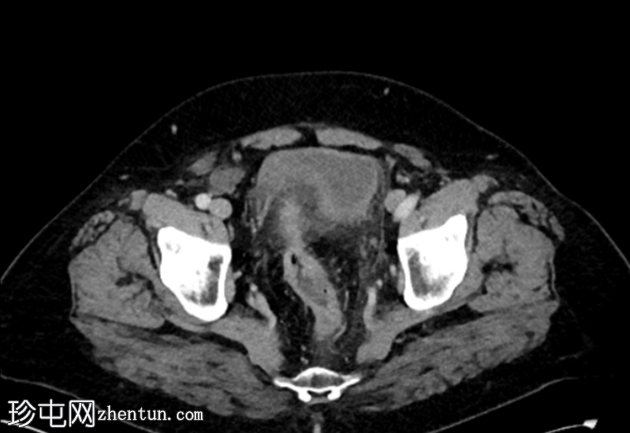

轴位增强扫描(门静脉期)

1.png

多发性乙状结肠憩室。

乙状结肠壁增厚,伴结肠周围脂肪条索影,左侧壁局部穿孔。未见肠外脓肿、腹水或气腹,提示IA期复杂性急性憩室炎。

脂肪肝。

胆囊切除术夹。

双侧肾盂周围及皮质囊肿,左侧较大。